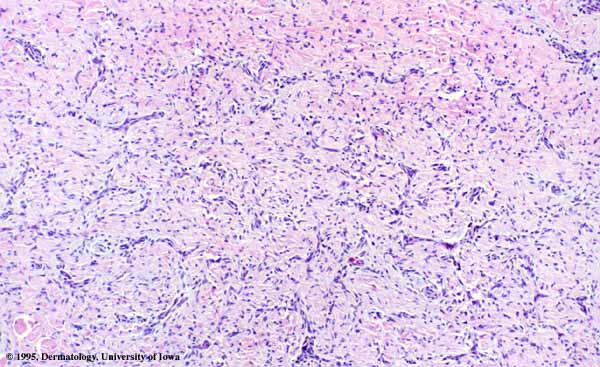

The bulk of the tumor is within the mid dermis where no capsule is present and the periphery of the lesion blends with the surrounding tissue. Whorling fascicles of a spindle cell proliferation with excessive collagen deposition are characteristic. At the periphery, the spindle cells characteristically wrap around normal collagen bundles (see the images below). Occasionally, melanocytes have been reported to be interspersed amongst the spindle cells.24

The subcutis typically is preserved, but if involved (especially when a storiform [cartwheel] pattern is observed), be alert to the possibility of the lesion being a dermatofibrosarcoma protuberans (DFSP).